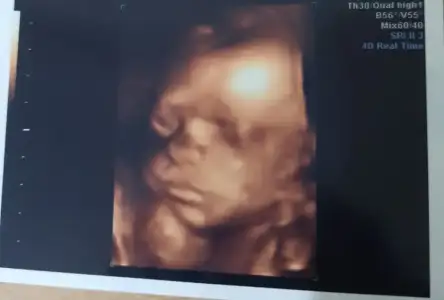

Slmlar herkese bizim bugun doktor ziyaret günümüzdu tam 26+0 810 grm 32 santimmisiz kafası sağ kaburgamın altindaymis ters duruyo dedi böbrek ağrın olursa panik yapma dedi bebis hep bi yerdeymis çünkü bu da resmimiz💕

• Screenshot_20220416-191945_Gallery.webp

Screenshot_20220416-191945_Gallery.webp

11,7 KB · Görüntüleme: 110